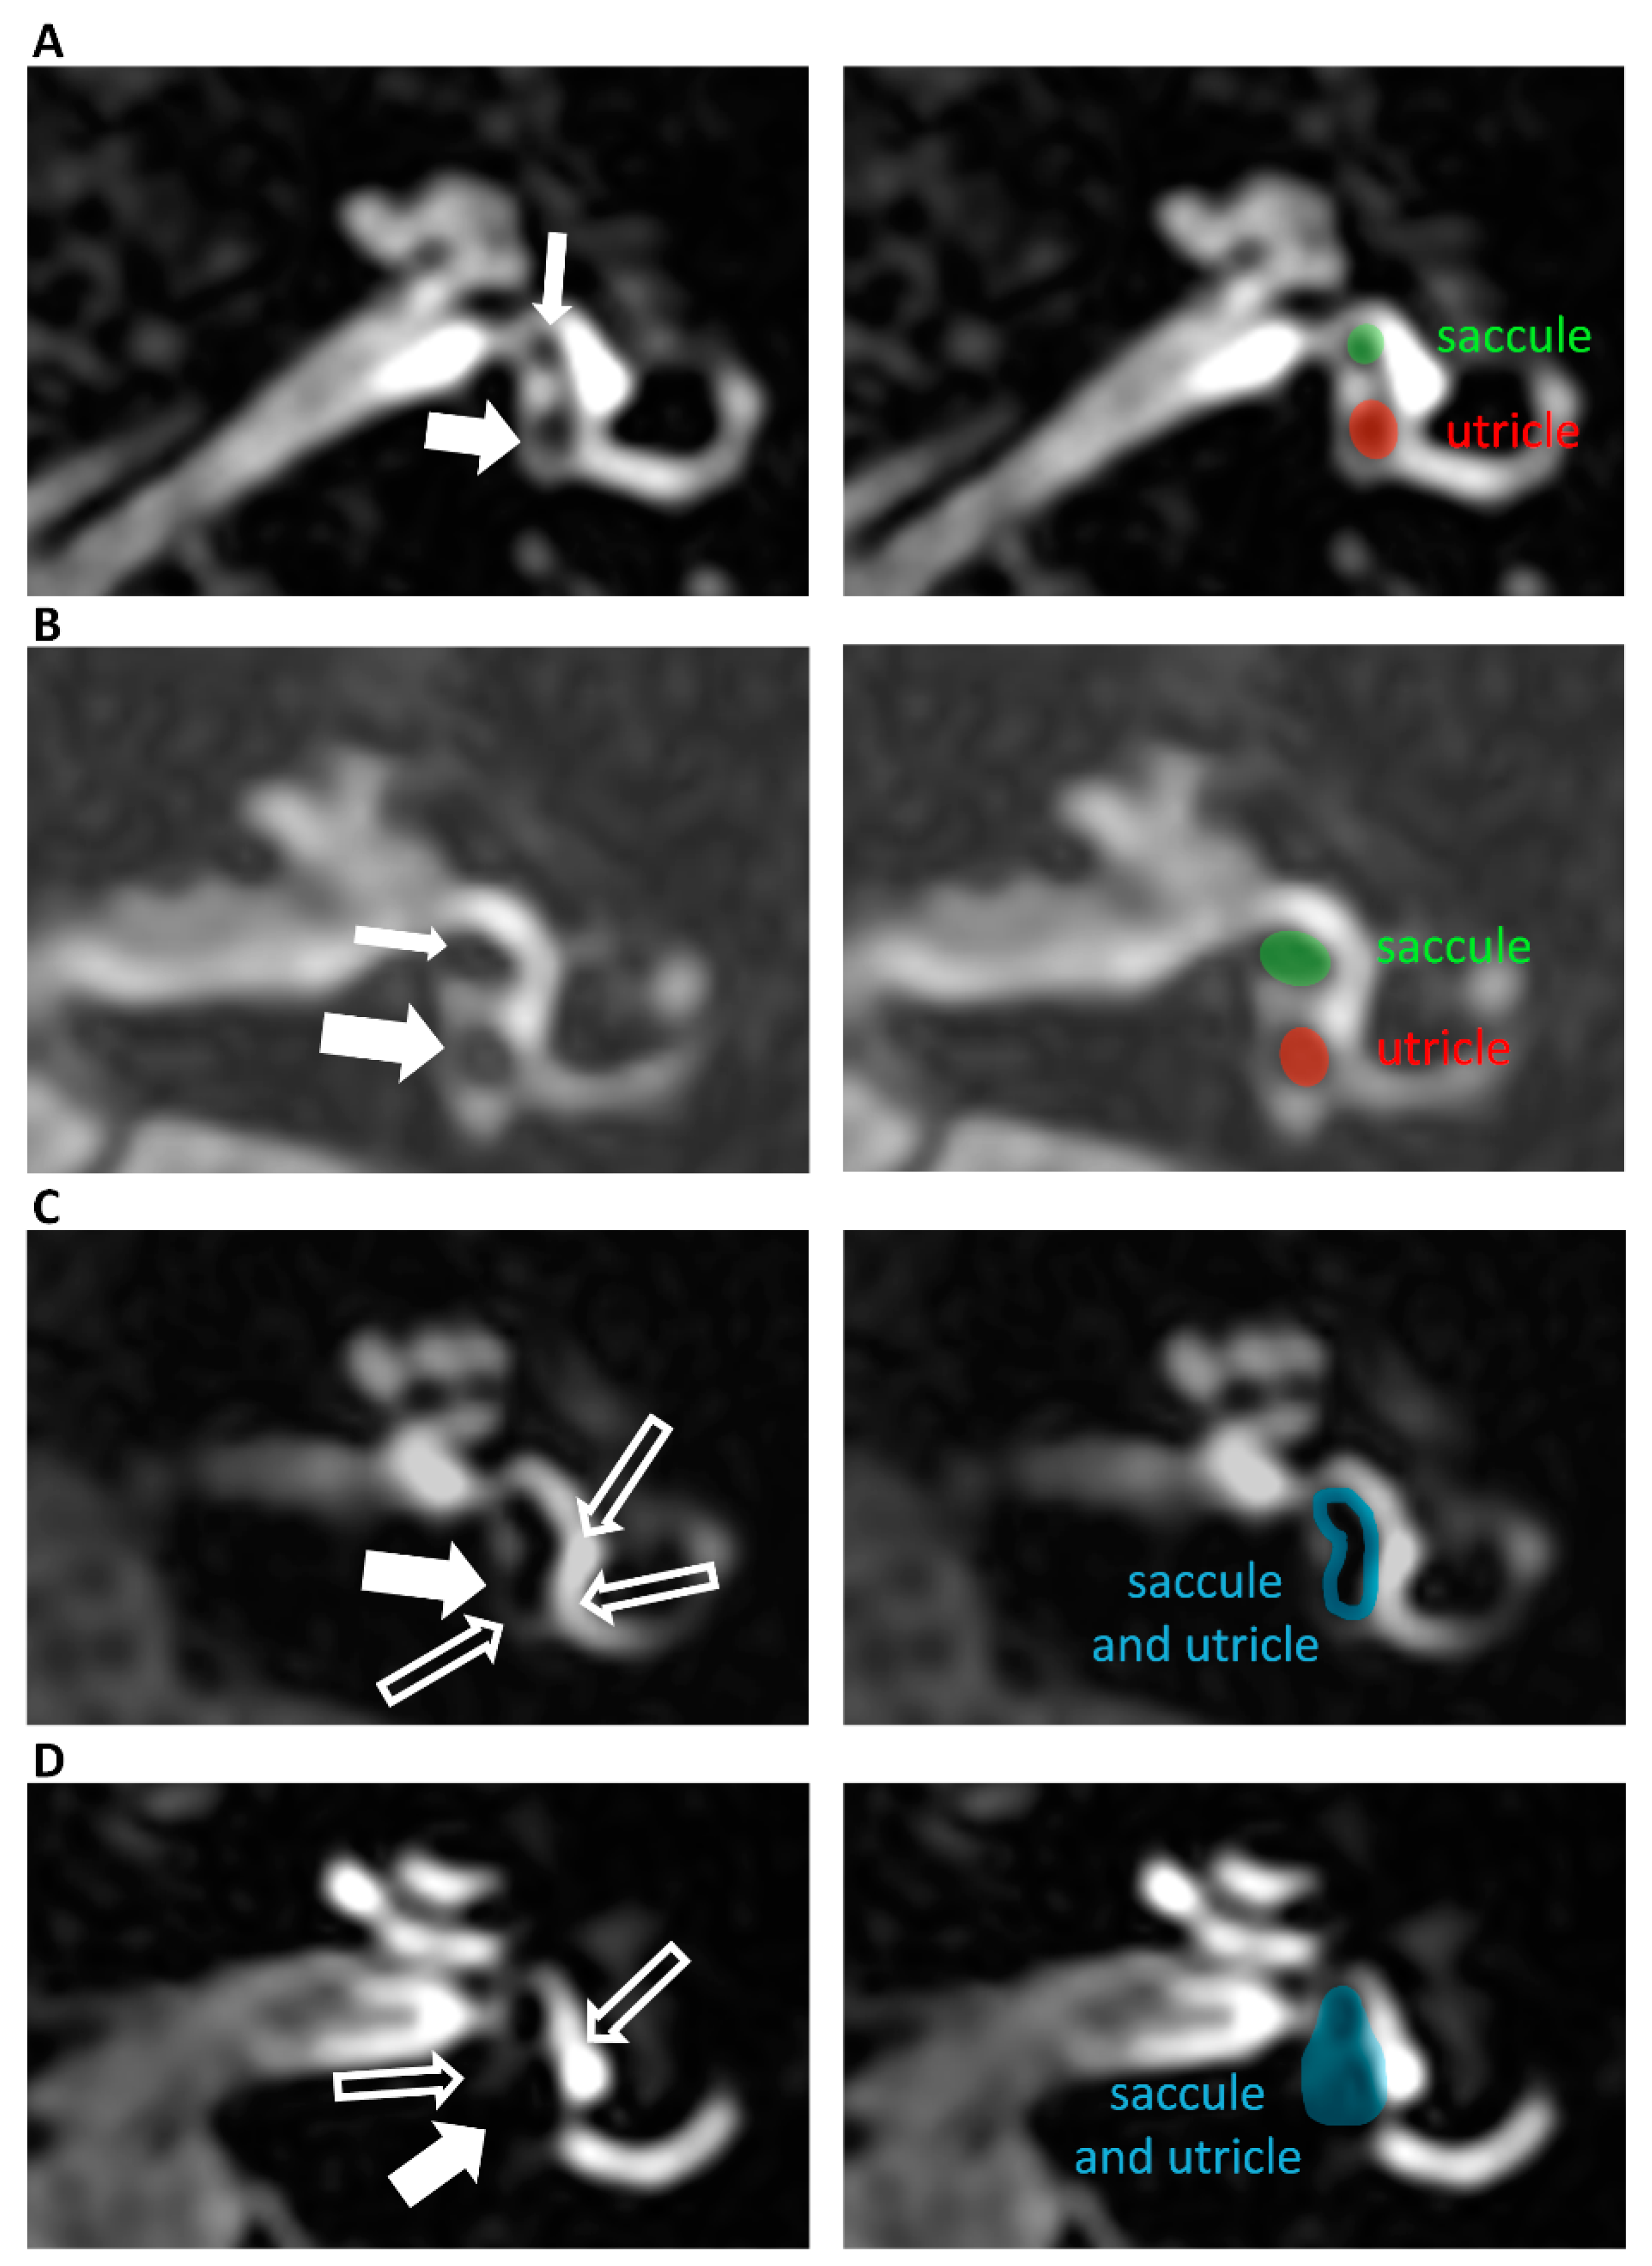

2.3. Magnetic Resonance Imaging Procedure and Analysis